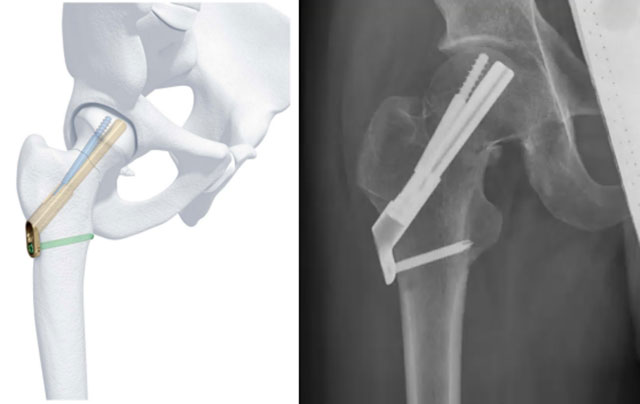

对于年轻患者股骨颈骨折也有新的方案:

①股骨颈骨折FNS内固定:与传统相比抗旋转能力明显提高,可以降低骨折不愈合的几率,提高骨折复位后的稳定性,操作上也比较简单,创伤也比较小,有利于股骨颈骨折患者的术后快速康复,是股骨颈不稳定性骨折的新选择。

股骨颈骨折FNS内固定